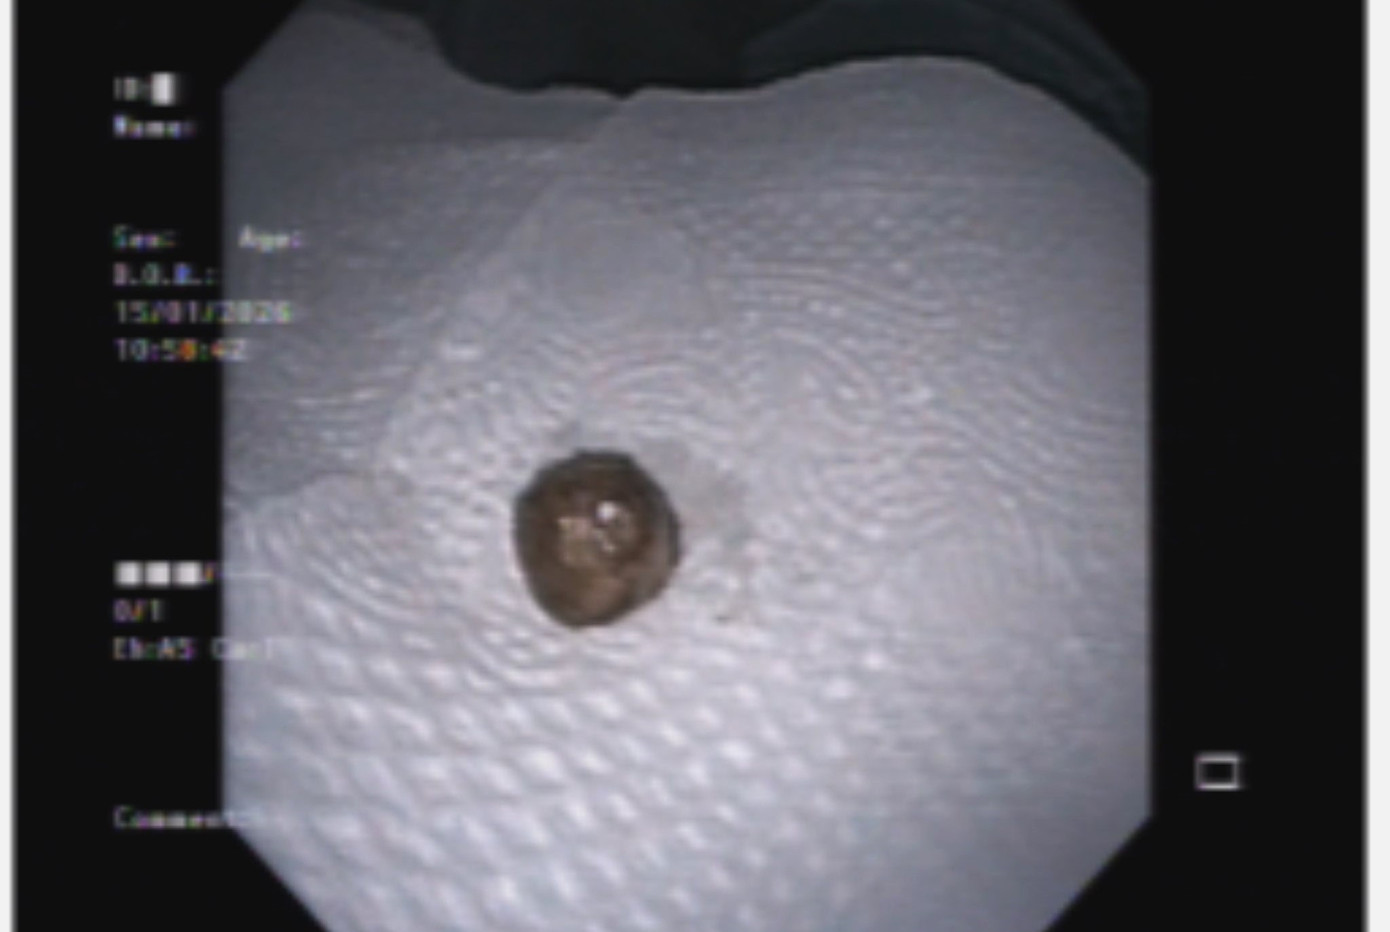

Bệnh nhân được chỉ định nội soi phế quản cấp cứu. Quá trình nội soi phát hiện dị vật lấp kín hoàn toàn phế quản gốc trái. Dị vật có tính chất mềm, dễ vỡ, tiềm ẩn nguy cơ rơi xuống các nhánh phế quản nhỏ nếu thao tác không cẩn trọng. Nhờ sử dụng các thiết bị nội soi chuyên dụng và sự phối hợp chặt chẽ giữa ê-kíp nội soi hô hấp và tiêu hóa, dị vật đã được lấy ra an toàn.

Dị vật là viên thuốc có dạng tròn, mềm, màu vàng, kích thước khoảng 10x10mm. Khai thác kỹ tiền sử ghi nhận bệnh nhân từng bị sặc khi uống một loại thuốc có hình dạng tương tự.

Dị vật được lấy ra.